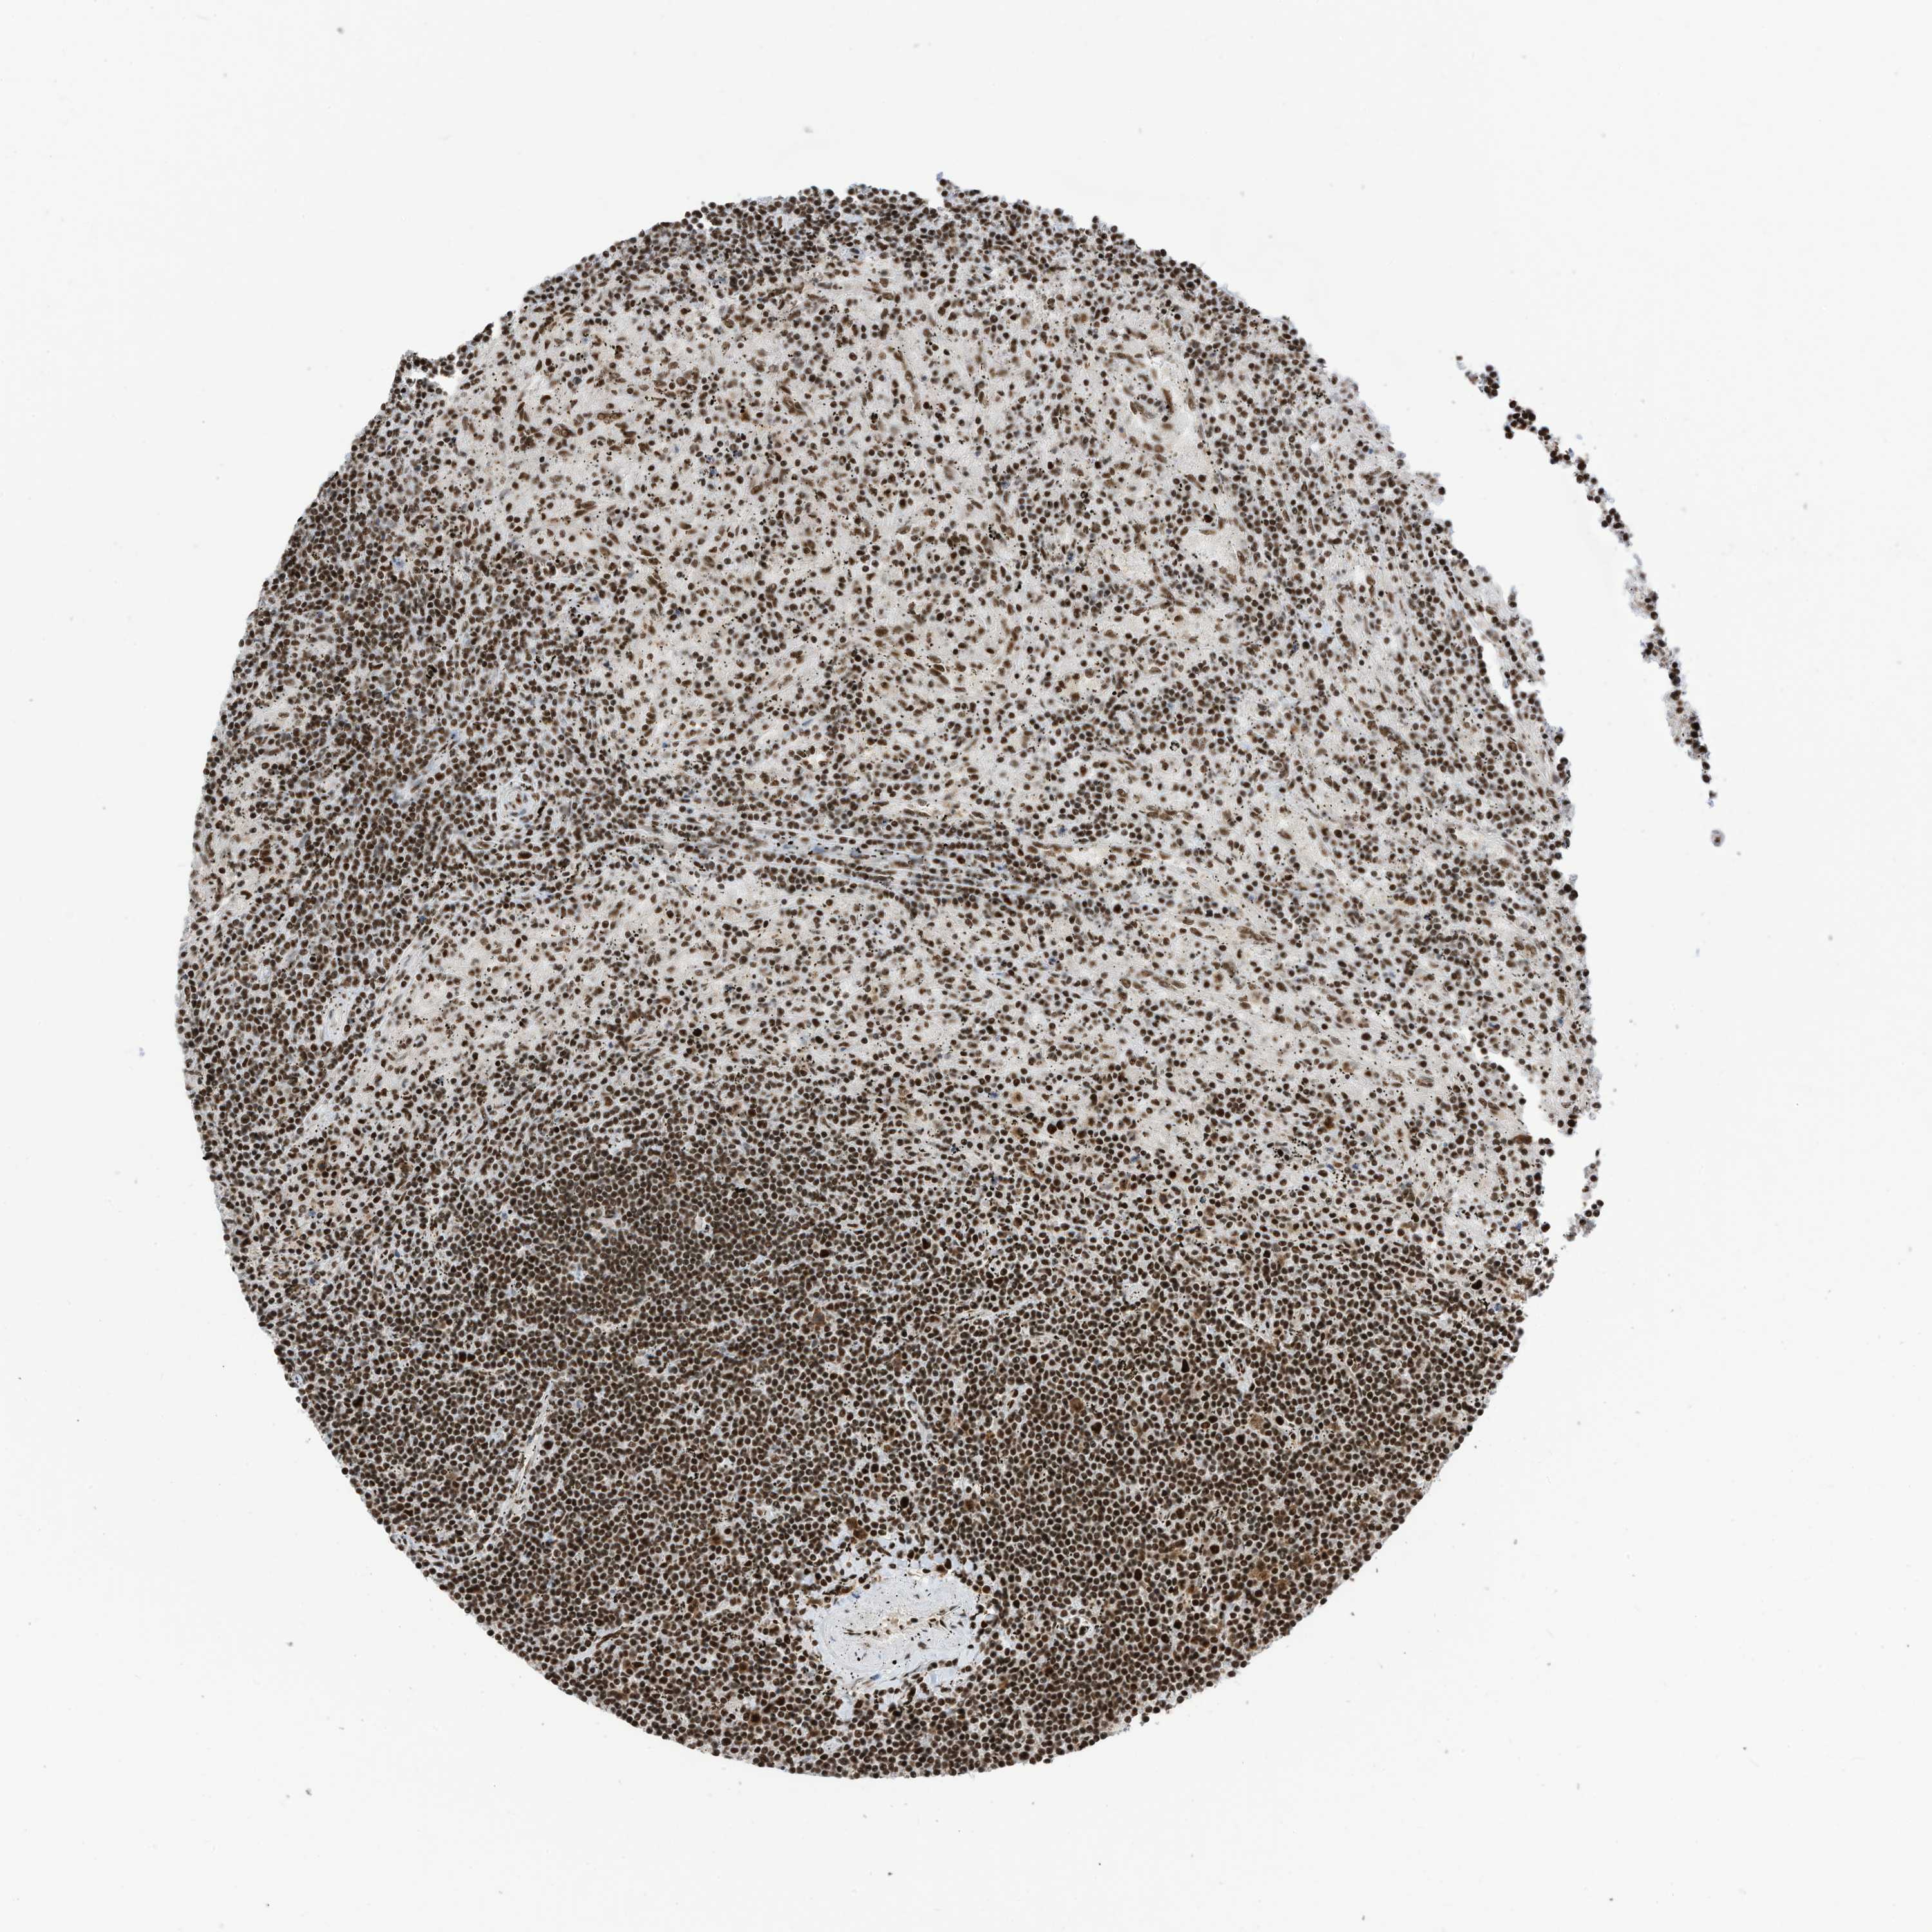

LYMPHOMA - Protein expressioni

A mouse-over function shows sample information and annotation data. Click on an image to view it in a full screen mode. Samples can be filtered based on level of antibody staining by selecting one or several of the following categories: high, medium, low and not detected. The assay and annotation is described here.

Antibody stainingi

Antibody staining in the annotated cell types in the current human tissue is reported as not detected, low, medium, or high, based on conventional immunohistochemistry profiling in selected tissues. This score is based on the combination of the staining intensity and fraction of stained cells.

Each image is clickable and will lead to virtual microscopy that enables deeper exploration of all samples and also displays staining intensity scores, fraction scores and subcellular localization as well as patient and tissue information for each sample.

Antibody HPA032055

Staining

High

Intensity

Strong

Quantity

>75%

Location

Nuclear

Hodgkin's disease, NOS

Malignant lymphoma, non-Hodgkin's type, High grade

Malignant lymphoma, non-Hodgkin's type, Low grade